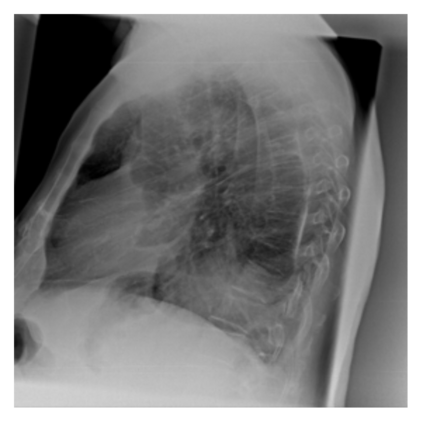

The evaluation of infectious disease processes on radiologic images is an important and challenging task in medical image analysis. Pulmonary infections can often be best imaged and evaluated through computed tomography (CT) scans, which are often not available in low-resource environments and difficult to obtain for critically ill patients. On the other hand, X-ray, a different type of imaging procedure, is inexpensive, often available at the bedside and more widely available, but offers a simpler, two dimensional image. We show that by relying on a model that learns to generate CT images from X-rays synthetically, we can improve the automatic disease classification accuracy and provide clinicians with a different look at the pulmonary disease process. Specifically, we investigate Tuberculosis (TB), a deadly bacterial infectious disease that predominantly affects the lungs, but also other organ systems. We show that relying on synthetically generated CT improves TB identification by 7.50% and distinguishes TB properties up to 12.16% better than the X-ray baseline.